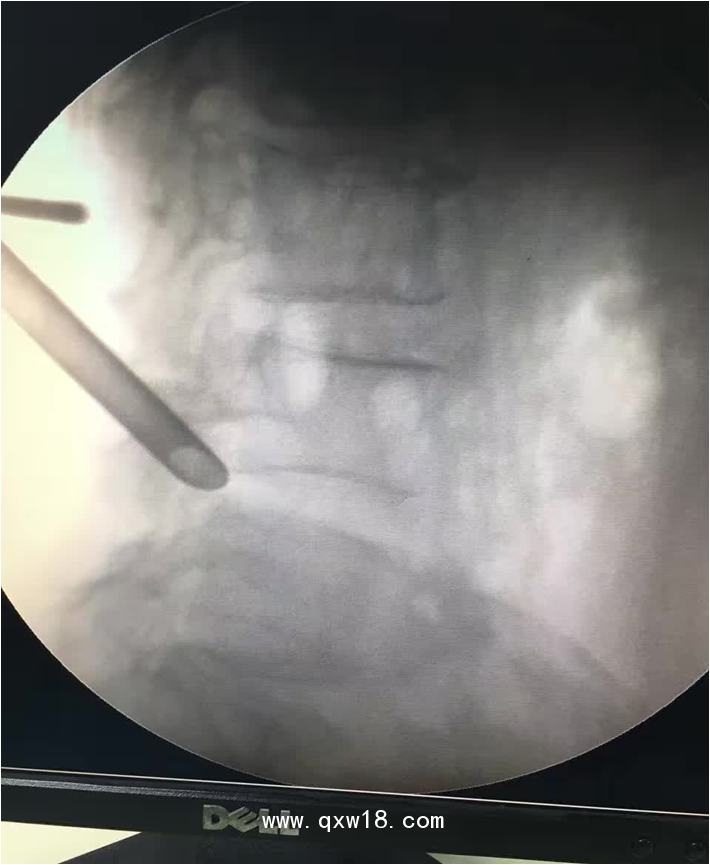

椎間孔鏡品牌椎間孔鏡椎間孔鏡技術(shù)椎間孔鏡培訓(xùn)產(chǎn)品說(shuō)明:

portant; word-wrap: break-word !important;">椎間孔鏡手術(shù)圍手術(shù)期注意事項(xiàng):